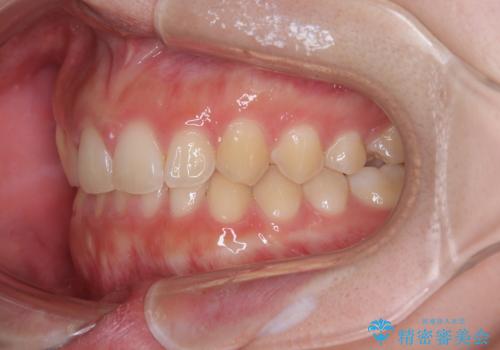

前歯のすきっ歯を治したい インビザラインによる矯正治療

- 上顎前歯の隙間を気にして来院された患者様です。

目立たない装置を希望とのことで、インビザラインを用いて矯正治療を行うこととしました。

一度インビザラインのマウスピースセットをお渡しすると1年以上来院されず、マウスピースを破損したり紛失したりすると来院されるというのんびりとしたペースで治療を行ったため、4年間という長期にわたる治療となりました。

最終的には隙間は全て閉じ、綺麗な仕上がりとなりました。